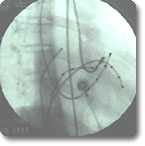

我科于1993年开展心内电生理及射频消融术,为室上性心动过速、房速、特发性室速及Ⅰ型房扑的患者解除了疾苦,是目前治疗这类心脏病患者的最好手段。它具有创伤小、治愈率高、几乎无严重并发症及住院时间短等优势。我科已累计开展心内电生理及射频消融术近1000例。 |